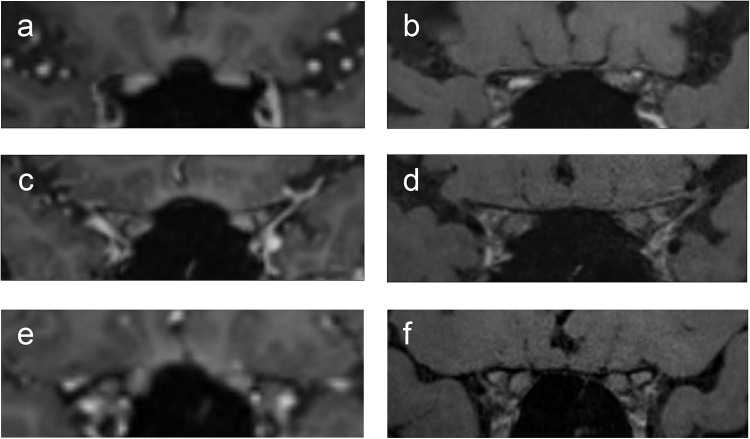

Patients and methods: Patients diagnosed with optic neuritis or non-arteritic anterior ischemic optic neuropathy (NA-AION) were evaluated at the Ophthalmology Department of Kyoto University Hospital. All patients underwent magnetic resonance (MR) studies before treatment initiation and ophthalmic examinations before and after treatment. Three ophthalmologists independently reviewed the MR scans for abnormalities. The magnetic resonance imaging (MRI) assessments included post-contrast DANTE T1-SPACE, post-contrast volumetric interpolated breath-hold examination (VIBE), and short T1 inversion recovery (STIR) scans. The presence of abnormalities in each sequence was determined.

Results: Of 36 eyes from 30 patients, 21 eyes from 17 patients were diagnosed with optic neuritis, and 15 eyes from 13 patients were diagnosed with NA-AION. DANTE T1-SPACE sequences showed better sensitivity for detecting optic neuritis than STIR sequences (100% vs 67%, p = 0.009). VIBE images did not confirm enhancement of lesions in some cases with optic neuritis. No differences were observed among the sequences for NA-AION. Lesion length evaluated by DANTE T1-SPACE sequences was associated with circumpapillary retinal nerve fiber layer thickness at the initial visit, eye pain, and the time interval from symptom onset to MRI scan.

Conclusion: Contrast-enhanced DANTE T1-SPACE was better than other sequences of MRI for diagnosing optic neuritis.